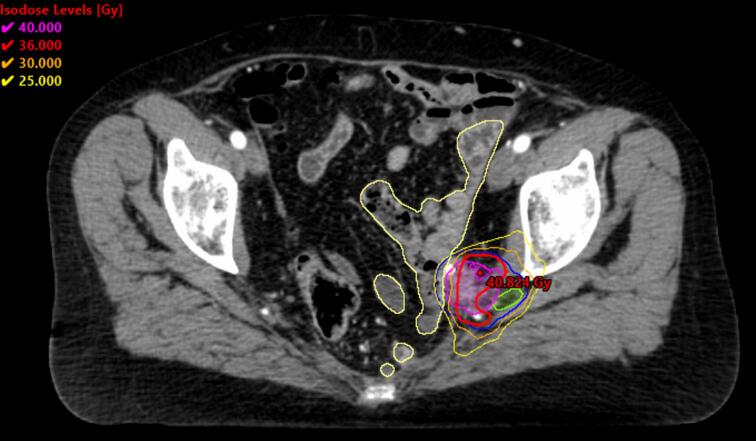

立体定向消融体放射治疗(SABR)通常用于治疗少转移性疾病。越来越多的有危险的目标或器官与以前的放射治疗领域重叠。由于临床实践中存在实质性的差异,英国SABR联盟与一个合作的国家小组合作制定了骨盆SABR再照射共识指南。指南的范围包括患者选择标准、治疗前注意事项、划定指南、剂量处方、累积剂量限制的计算和最佳规划技术。该指南是与皇家放射科医师学院和EORTC ReCare合作进行的国家前瞻性审计的一部分。

Stereotactic ablative body radiotherapy (SABR) is routinely used for the management of oligometastatic disease. Increasingly, there is overlap of targets or organs at risk with previous radiotherapy fields. As substantial variation in delivery of clinical practice exists, the UK SABR Consortium worked with a collaborative national group to develop pelvic SABR re-irradiation consensus guidelines. The scope of the guidance includes patient selection criteria, pre-treatment considerations, delineation guidelines, dose prescription, calculations of cumulative dose constraints, and optimal planning technique. This guidance is part of an ongoing national prospective audit in collaboration with the Royal College of Radiologists and EORTC ReCare.